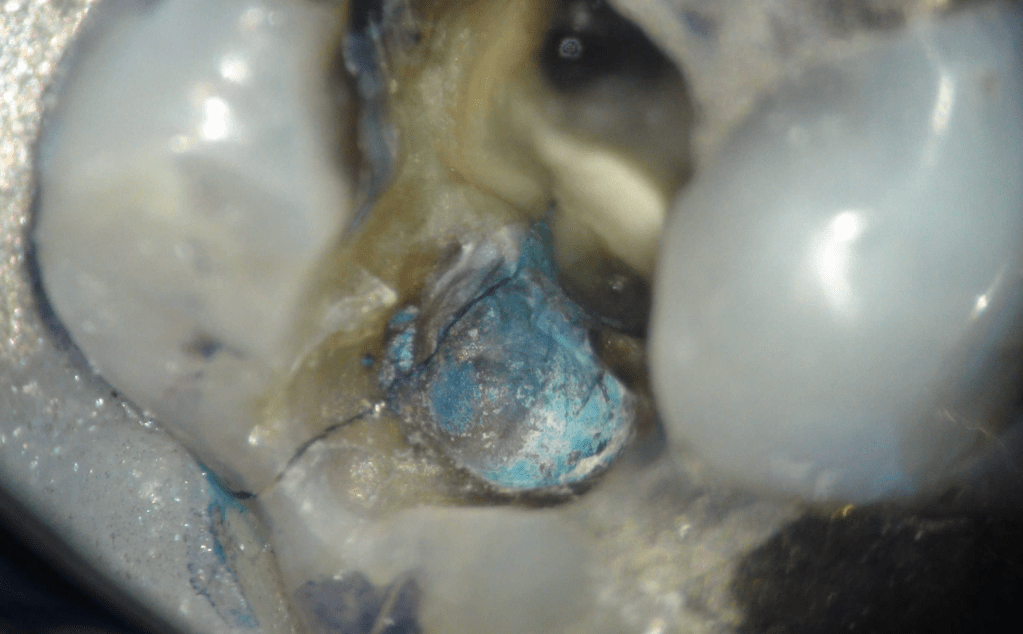

Fisura, remoción amalgama para explorar